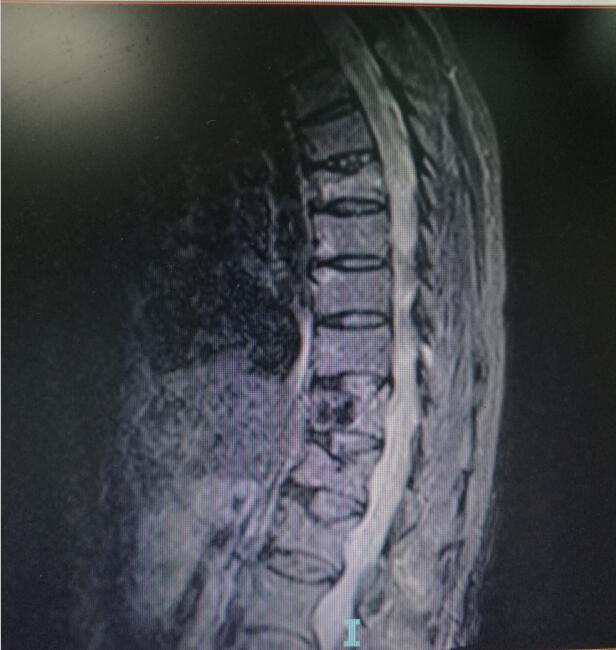

術(shù)前MRI(核磁共振檢查)

“經(jīng)骨二科收治入院,完善相關(guān)檢查后,明確診斷為老年性骨質(zhì)疏松性胸腰椎壓縮骨折,這是發(fā)生在老年人身上的一個常見病,科室對此類病例具有成熟的治療經(jīng)驗?!?據(jù)瀘州市中醫(yī)醫(yī)院骨傷二科副主任中醫(yī)師唐國皓介紹,醫(yī)護(hù)人員經(jīng)過與患者耐心溝通,迅速確定了手術(shù)治療方案。

入院后第四天,由骨傷二科副主任楊陳一、劉永森醫(yī)生、唐國皓醫(yī)生聯(lián)合為患者成功實施了微創(chuàng)下的經(jīng)皮穿刺椎體后凸成形術(shù)。術(shù)后,患者腰背部疼痛逐漸緩解,術(shù)后第二天即下床活動。